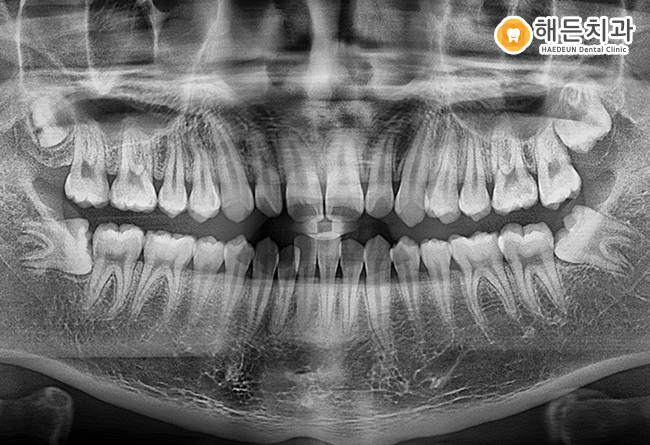

치아 통증으로 해든치과에 내원하신 환자분의 사례로,

파노라마 및 구강 사진을 통해 해당 치아가

정상적인 방향이 아닌 옆으로 기울어진 상태에서

일부만 맹출한 양상을 확인할 수 있었습니다.

.

이처럼 치아가 절반 정도만 올라온 경우에는

앞쪽 어금니와의 사이에 음식물이나 이물질이

쉽게 끼는 환경이 형성되며,

관리가 어려워지는 경향이 나타납니다.